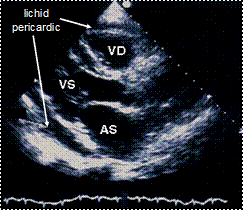

Ecocardiografice

clivare de spatiu pericardic sau spatiu transsonic (lichid) de diverse grosimi si localizari;

ingrosare de pericard cu eventuale depozite de fibrina (uneori libere in lichid).

Semne ecocardiografice:

lichid pericardic in cantitate mare (evidentiaza si dispunerea topografica a acestuia),

reducere a amplitudinii excursiei DE si pantei EF a valvei mitrale la prima diastola din inspir,

variatie inspir-expir > 40% a amplitudinii excursiei DE a valvei tricuspide,

colaps AD, VD (protodiastolic) si AS,

congestie 'fixa' a VCI (scadere < 50% in diametru proximal la inspir profund).

EcoCG in tamponada cardiaca